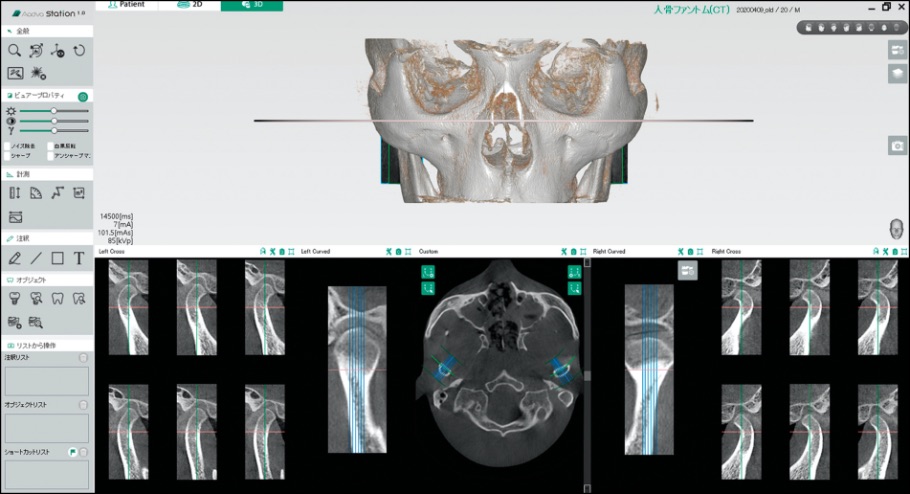

TMJ Viewer

TMJビューアーでは、3Dボリュームレンダリング画像と左右顎関節のクロスセクション画像を同時に比較参照することができます。